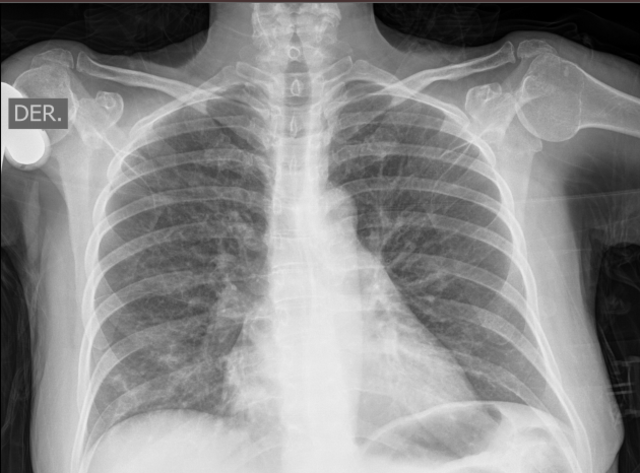

Plan: BK1 // Hemogrma//G-U-C//RX TORAX// I/C INTELIGENCIA SANITARIA e INFECTOLOGÍA

ACTUALIZA ANALITICA, RX TORAX